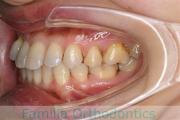

No.14V-516

- 主な症状:

- 上顎前突

- その他の症状:

- 叢生

- 年齢:

- 10歳

- 性別:

- 女性

- 抜歯部位

- 上:

- 44

- 下:

- 55

- 主な使用装置:

- FEA

- 治療にかかった費用:

- 90万円

きれいな歯並びにしたいということで来院されました。第一期治療で六歳臼歯の位置を維持する装置を入れて第二期治療の準備をしました。第二期は中学生になってから小臼歯を抜歯して行いました。二期治療は約2年半、25回程度の通院が必要でした。

- ≫治療後

二期治療開始前は叢生(でこぼこ、凹凸、ガタガタ)がかなりありましたので、保定をしっかりしないと段差ができてきたり後戻りのリスクがあります。